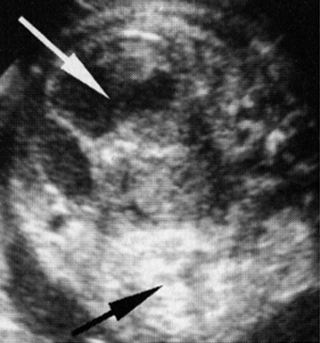

Υπερηχογραφικά, οι δύο νεφροί εμφανίζονται διογκωμένοι και υπερηχογενείς με

αναρίθμητες κύστεις στο φλοιό, διαμέτρου <2mm. Η έντονη υπερηχογένεια αποδίδεται

στην ενίσχυση των υπερήχων από τις μικροσκοπικές κύστεις (εικόνες 4, 5). Η νόσος

είναι αμφοτερόπλευρη και συμμετρική, αλλά υπερηχογραφική απεικόνιση της νόσου

μπορεί να μην είναι δυνατή πριν τις 24 εβδομάδες, γι' αυτό, συνεχόμενα υπερηχογραφήματα

απαιτούνται για να αποκλεισθεί η διάγνωση. Άλλα διαγνωστικά κριτήρια είναι η

απουσία της ουροδόχου κύστης και το ολιγοάμνιο.

| Εικόνα

4. Potter I, εγκάρσια διατομή. |

Εικόνα

5. Potter I, επιμήκης διατομή. |